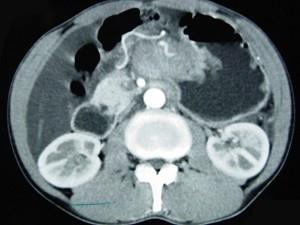

问题 男,65岁,中上腹痛腹胀、消瘦、乏力、纳差,影像检查如图,最可能的诊断是 ( )

选项 A、胃窦癌 B、胃淋巴瘤 C、萎缩性胃炎 D、肥厚性胃炎 E、胃间质瘤

答案 A